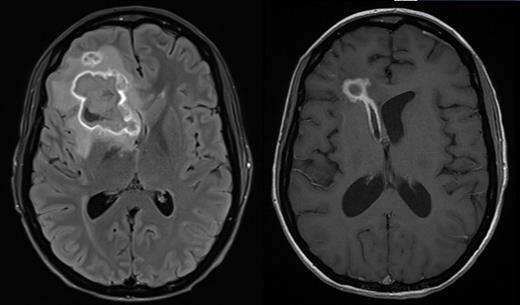

Patient A is a 27 year old female who underwent a myeloablative sibling haploidentical transplant for Philadelphia negative B-ALL in second remission. At day 100 she developed grade III lower GI GVHD requiring methylprednisolone and ruxolitinib for steroid dependent disease. Subsequent CMV reactivation was treated with ganciclovir. Cough in association with pulmonary infiltrates followed, and a bronchoalveolar lavage grew Scedosporium aurantiacum, Clavispora lusitaniaand Aspergillus fumigatus. She developed severe headache and MRI imaging showed a thin rim-enhancing 38x37 mm lesion within the right frontal lobe with moderate vasogenic oedema. Surgical drainage yielded 20 ml of frank pus that grew Scedosporium aurantiacum.

Antifungal therapy was started with vorinconazole, terbinafine, amphotericin and later caspofungin. Serial imaging after 12 days showed two new hyperdense foci representing extension of infection, consistent with worsening headaches. The patient received a single infusion of 3 rd party FSTs at a dose of 1 x10 6/m 2 at day 170 post-transplant while continuing antifungal therapy with vorinconazole and terbinafine. The product consisted of 94.1% CD4 +, 3.5% CD8 + T-cells and 1% NK cells and contained CD4 + T-cells responsive to both A. terreus and C. krusei antigens presented by HLA DR*03:01 shared between product and patient. There were no infusion related adverse events. Corticosteroids and calcineurin inhibitors were continued. Within one week of FST infusion there was an increase in the number of naïve and central memory CD4 + T-cells in blood and a fall in the number of CD4 + and CD8 + T-cells expressing Tim3. Over the following 3 months, there was a gradual rise in the number of CD4 + Tem and CD4 + Temra with a later and less pronounced rise in the analogous CD8 + populations. Serial imaging demonstrated rapid regression of the pulmonary abnormalities and gradual regression of the cerebral lesion at day 150 following FST infusion. 279 days after transplant and 109 days after infusion of FSTs, the patient developed worsening of headache and MRI confirmed rupture of the abscess into the right ventricle. Headache gradually resolved and the patient was discharged from hospital 329 days after transplant with ECOG 1 and no neurological abnormalities. However she was readmitted 13 days later with more severe headache with repeat imaging confirming raised intracranial pressure. CSF showed no evidence of fungi by PCR or culture. A CSF shunt was inserted and the patient remains well.